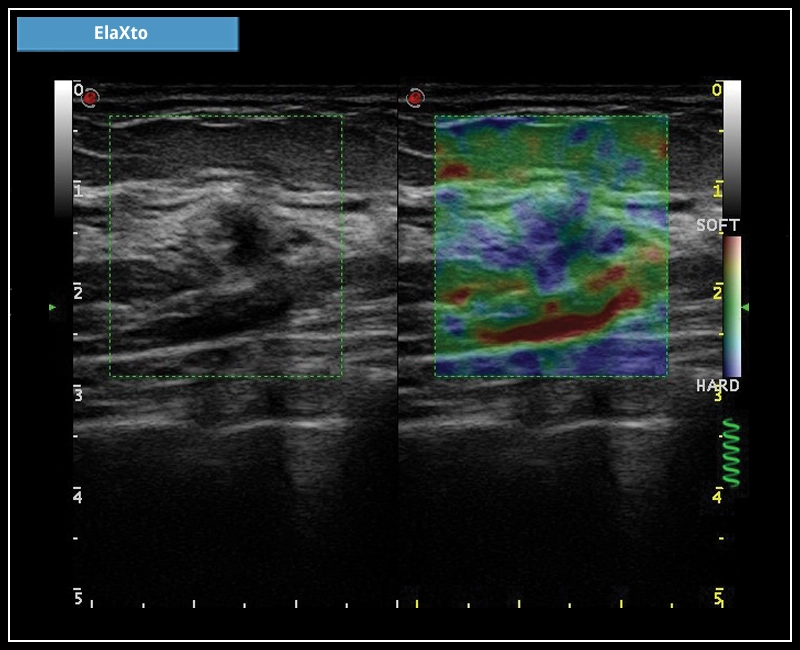

MyLab™C25 - ElaXto in breast

MyLab™C25 - ElaXto in breast

MyLab™9 Platform - Dual ElaXto characterization on breast lesion

MyLab™9 Platform - Dual ElaXto characterization on breast lesion

MyLab™9 Platform - Elastography advanced measurement package on breast lesion

MyLab™9 Platform - Elastography advanced measurement package on breast lesion

MyLab™Omega eXP - ElaXto

MyLab™Omega eXP - ElaXto

MyLab™X8 Platform - Lesion with ElaXto

MyLab™X8 Platform - Lesion with ElaXto

MyLab™X6 - ElaXto

MyLab™X6 - ElaXto

MyLab™X7 - ElaXto

MyLab™X7 - ElaXto

MyLab™Omega - Dual ElaXto on breast cyst

MyLab™Omega - Dual ElaXto on breast cyst